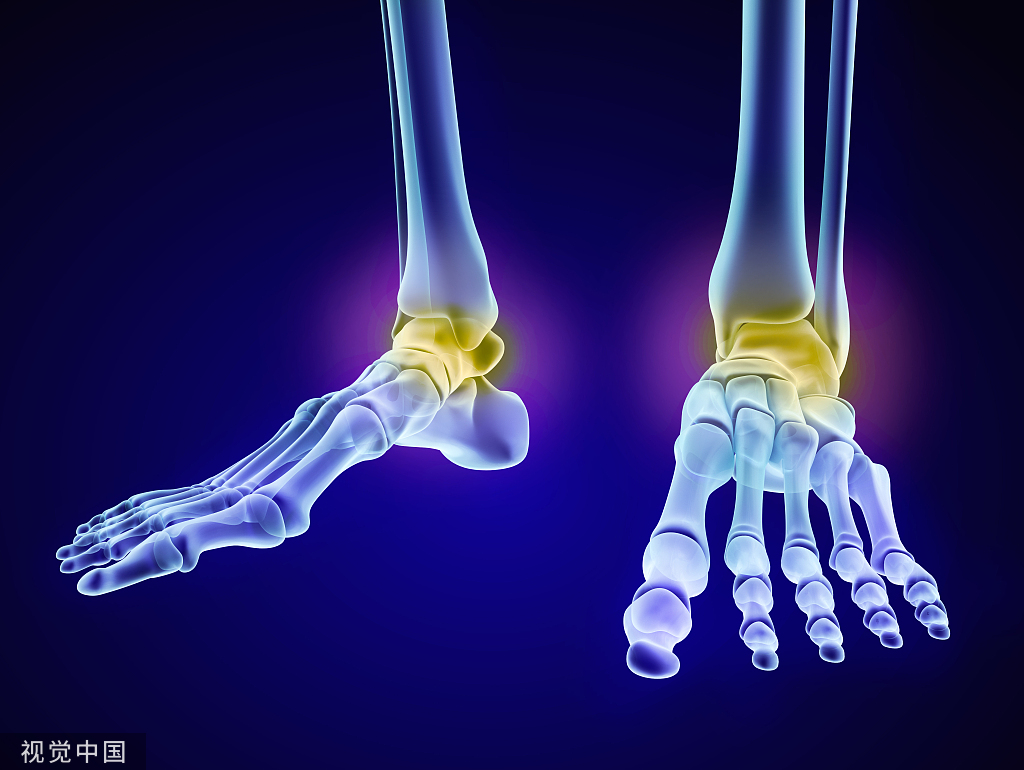

随着医疗水平的进步及人们对生活水平要求的提高,骨科创伤的治疗不仅需要完成局部组织的修复重建,更需要实现机体的快速康复。针对下肢骨科手术,早期进行合理的负重锻炼是术后管理的重要组成部分。合理负重不仅有助于局部骨质及软组织愈合,还可以促进患者整体机能恢复,提高医疗服务效率。然而,在临床实际操作中,如何让下肢术后患者合理负重一直是困扰医生及患者的难题,业内对于下肢术后负重基本理念及注意要点尚未达成共识。

针对此临床问题,由全国创伤骨科专家代表讨论总结了临床中术后负重现有的普遍问题,形成了下肢骨折术后合理负重的基本原则及专家建议,同时列举了针对下肢各部位的负重参考方案,以期指导骨科下肢术后负重临床实践,规范临床研究及相关技术发展,为骨折下肢创伤患者提供更加优质、高效的医疗服务。